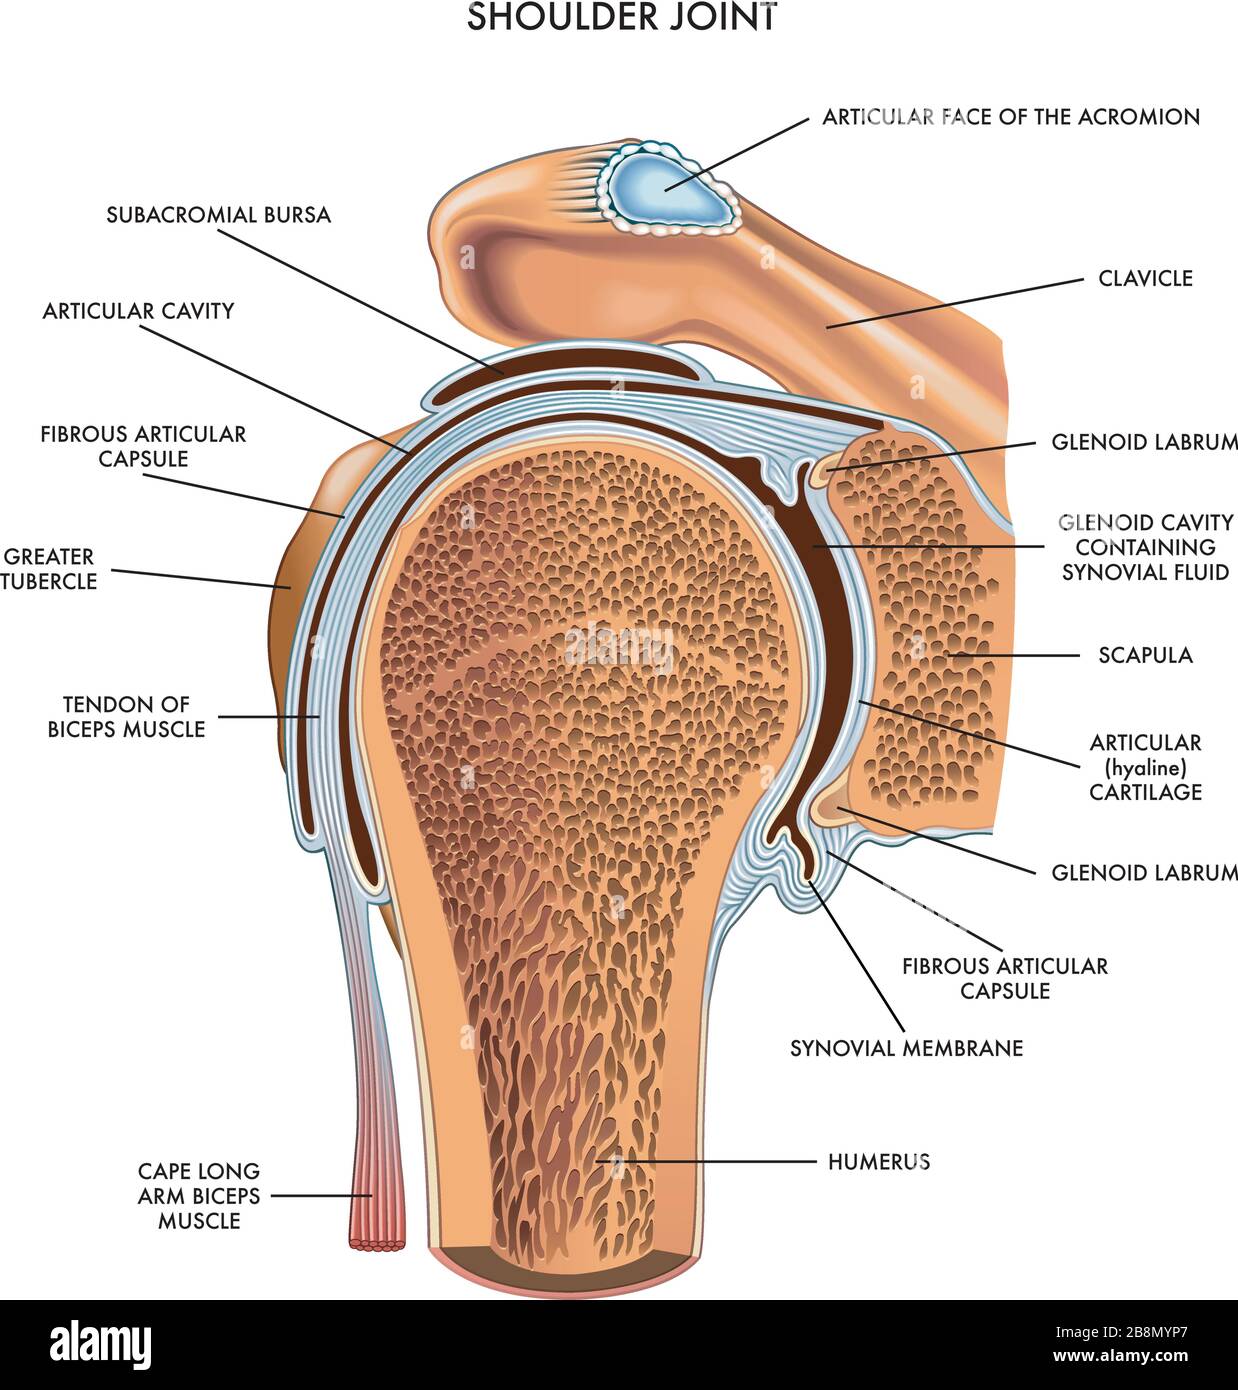

Shoulder joint illustrated and annotated with components on white. Stock Vectorhttps://www.alamy.com/image-license-details/?v=1https://www.alamy.com/shoulder-joint-illustrated-and-annotated-with-components-on-white-image349585439.html

Shoulder joint illustrated and annotated with components on white. Stock Vectorhttps://www.alamy.com/image-license-details/?v=1https://www.alamy.com/shoulder-joint-illustrated-and-annotated-with-components-on-white-image349585439.htmlRF2B8MYP7–Shoulder joint illustrated and annotated with components on white.

Anatomy of left shoulder, coronal view. Stock Photohttps://www.alamy.com/image-license-details/?v=1https://www.alamy.com/stock-photo-anatomy-of-left-shoulder-coronal-view-84250591.html

Anatomy of left shoulder, coronal view. Stock Photohttps://www.alamy.com/image-license-details/?v=1https://www.alamy.com/stock-photo-anatomy-of-left-shoulder-coronal-view-84250591.htmlRFEW1XDK–Anatomy of left shoulder, coronal view.